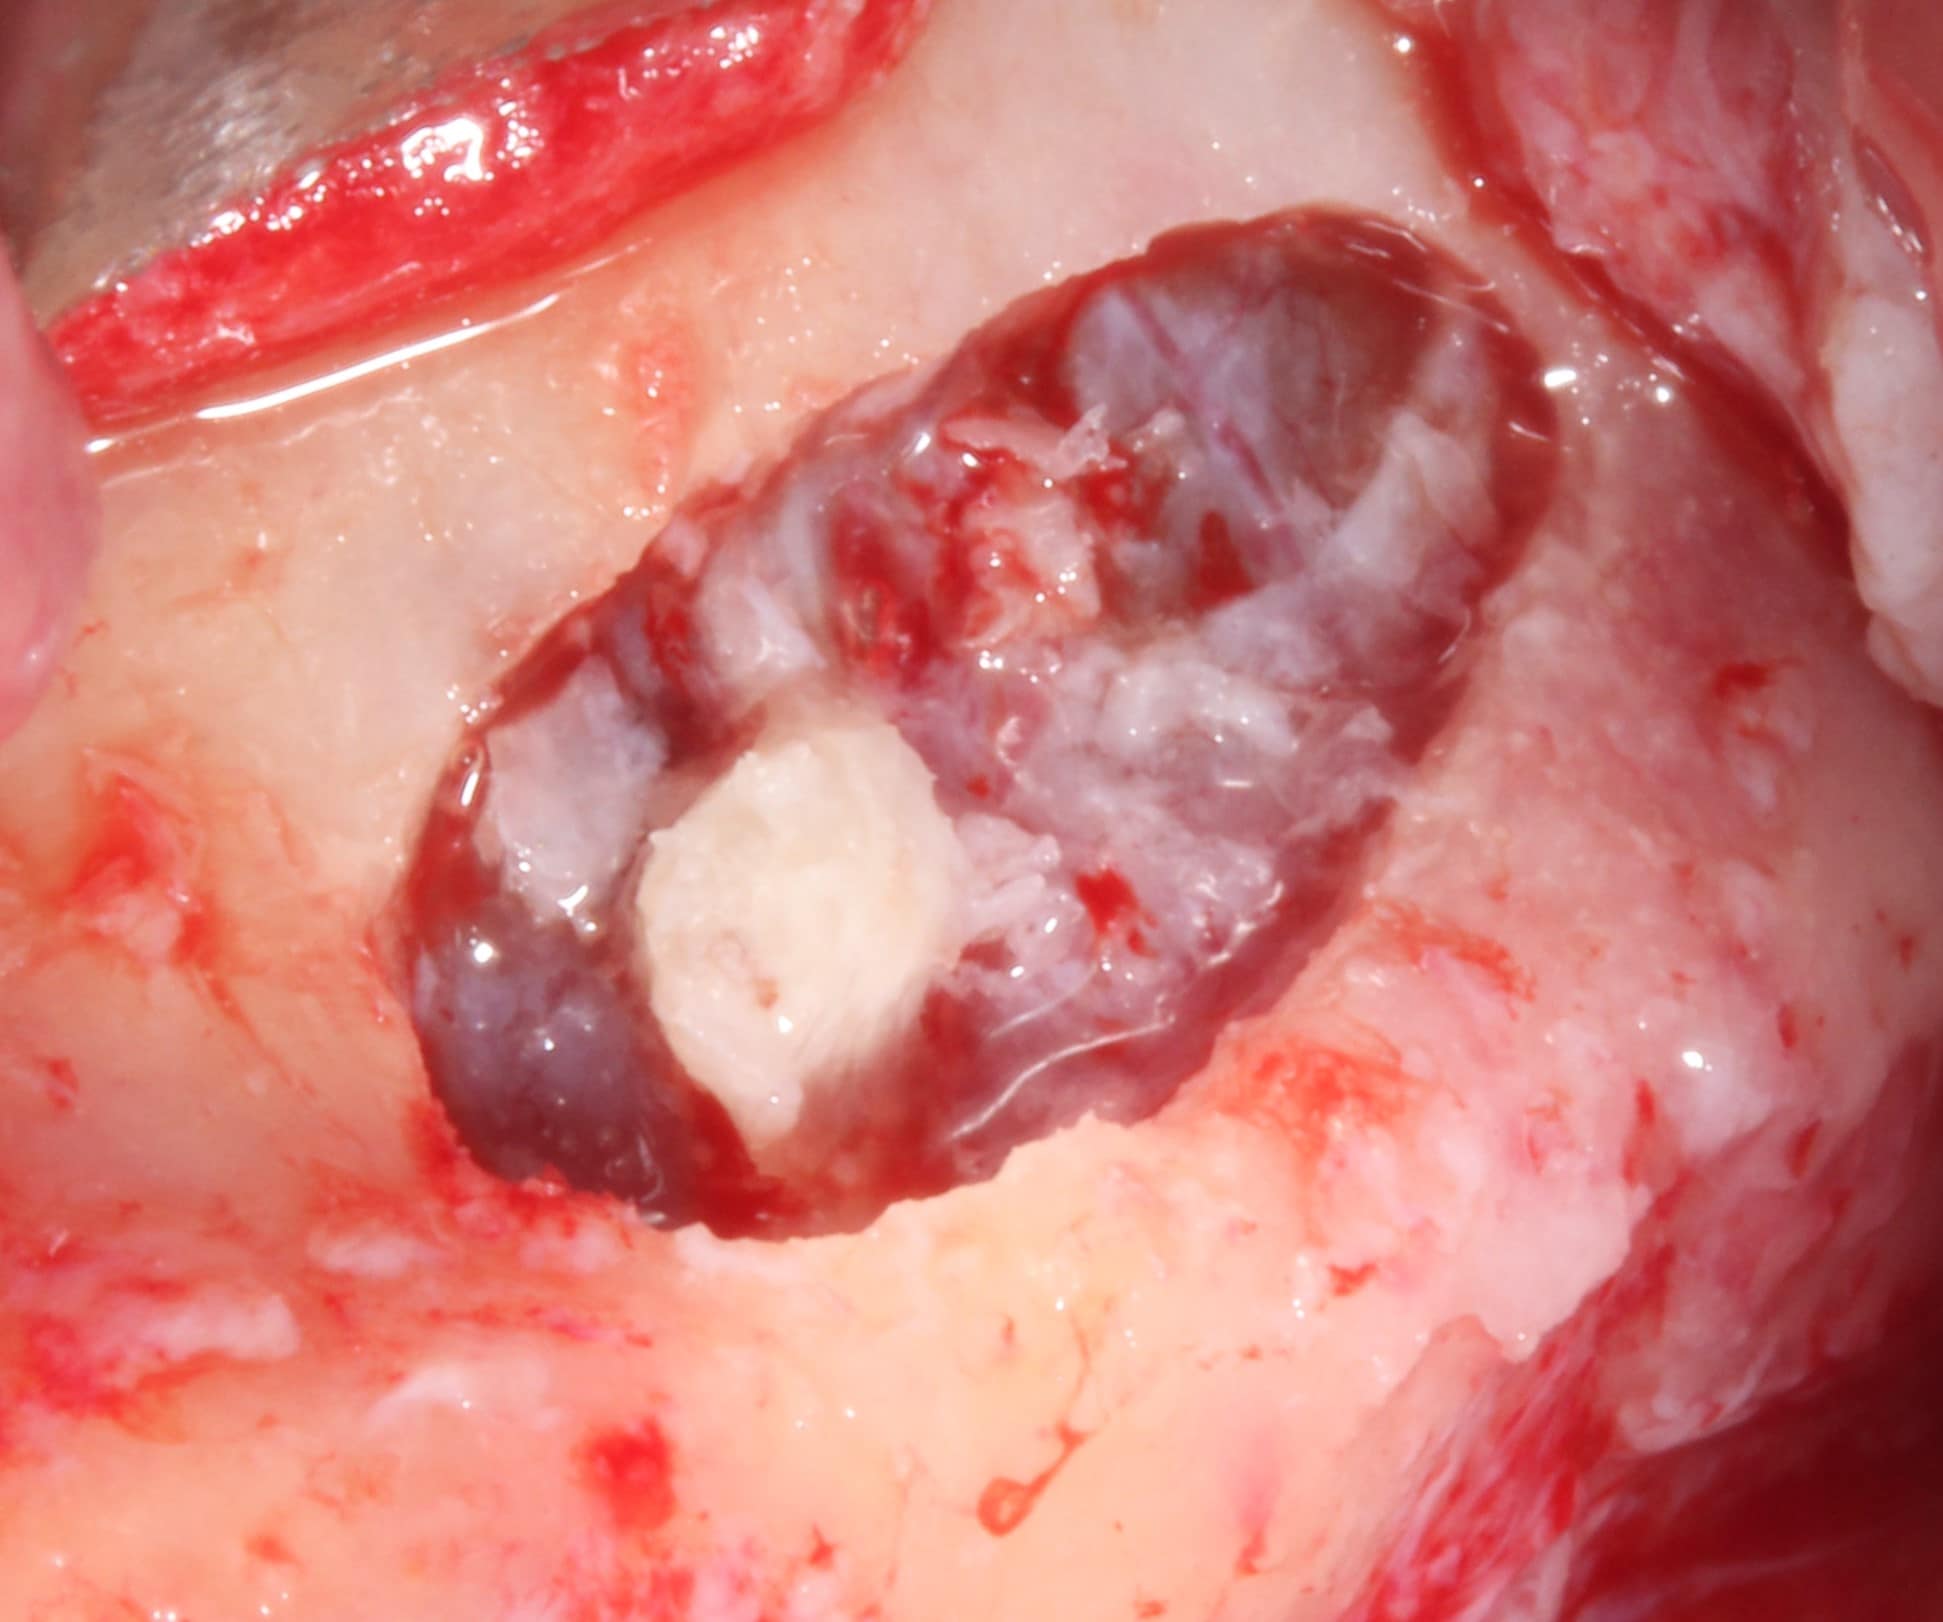

Comblement et élévation du sinus maxillaire

La SFBSI, organisme de formation professionnelle agréé par le CNFCO, vous propose un cycle complet de formation sur la technique chirurgicale du comblement de sinus.

Nous dispensons des cours théoriques aux chirurgiens-dentistes, stomatologistes et chirurgiens maxillo-faciaux sur les bases de l’implantologie et la technique du comblement du sinus maxillaire :

• l’anatomie et la physiopathologie du sinus ;

• la cicatrisation osseuse ;

• le matériau de comblement.

Nous animons également plusieurs travaux pratiques (occlusodontie, parodontologie, pose d’implants dentaires sur pièces anatomiques humaines…) et des démonstrations cliniques à l’Hôpital de Montreuil et dans les cabinets pilotes.